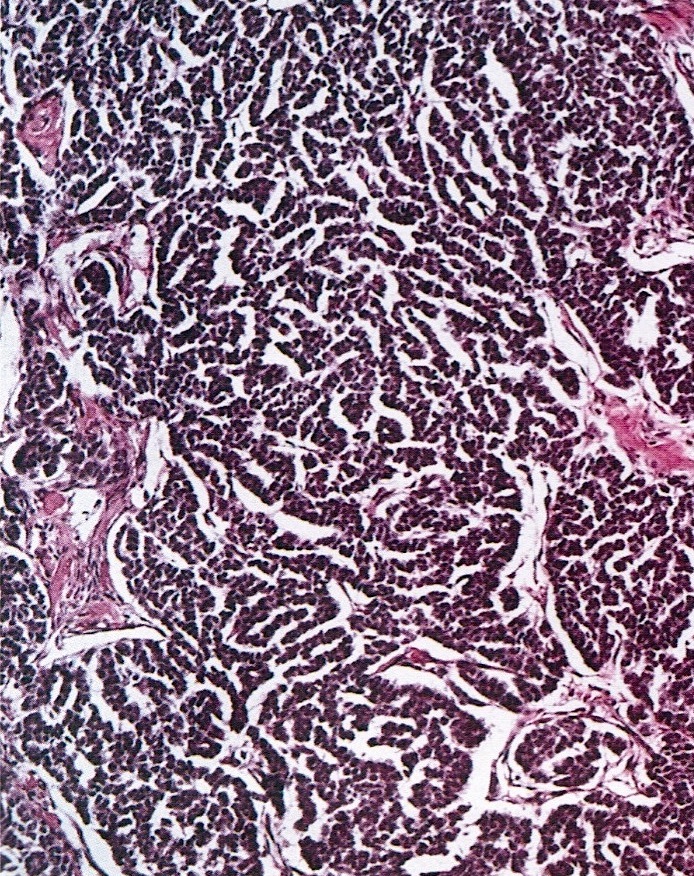

- Small, bland, cuboidal to polygonal cells with scant cytoplasm and pale, uniform angulated and usually grooved nuclei (coffee bean)

- Various patterns, including diffuse (the most common), trabecular and corded, insular, microfollicular (resembling Call-Exner bodies of the Graafian follicles: small follicle-like structures filled with eosinophilic material) and macrofollicular (the least common)

- Usually a mixed growth pattern is seen

Microscopic (histologic) images

Contributed by Shabnam Zarei, M.D. and Sharon Bihlmeyer, M.D.

AFIP images